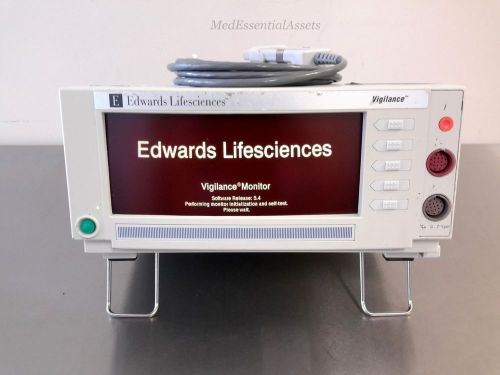

Edward LifeSciences Vigilance VGS Continuous Cardiac Advanced Patient Monitor OR